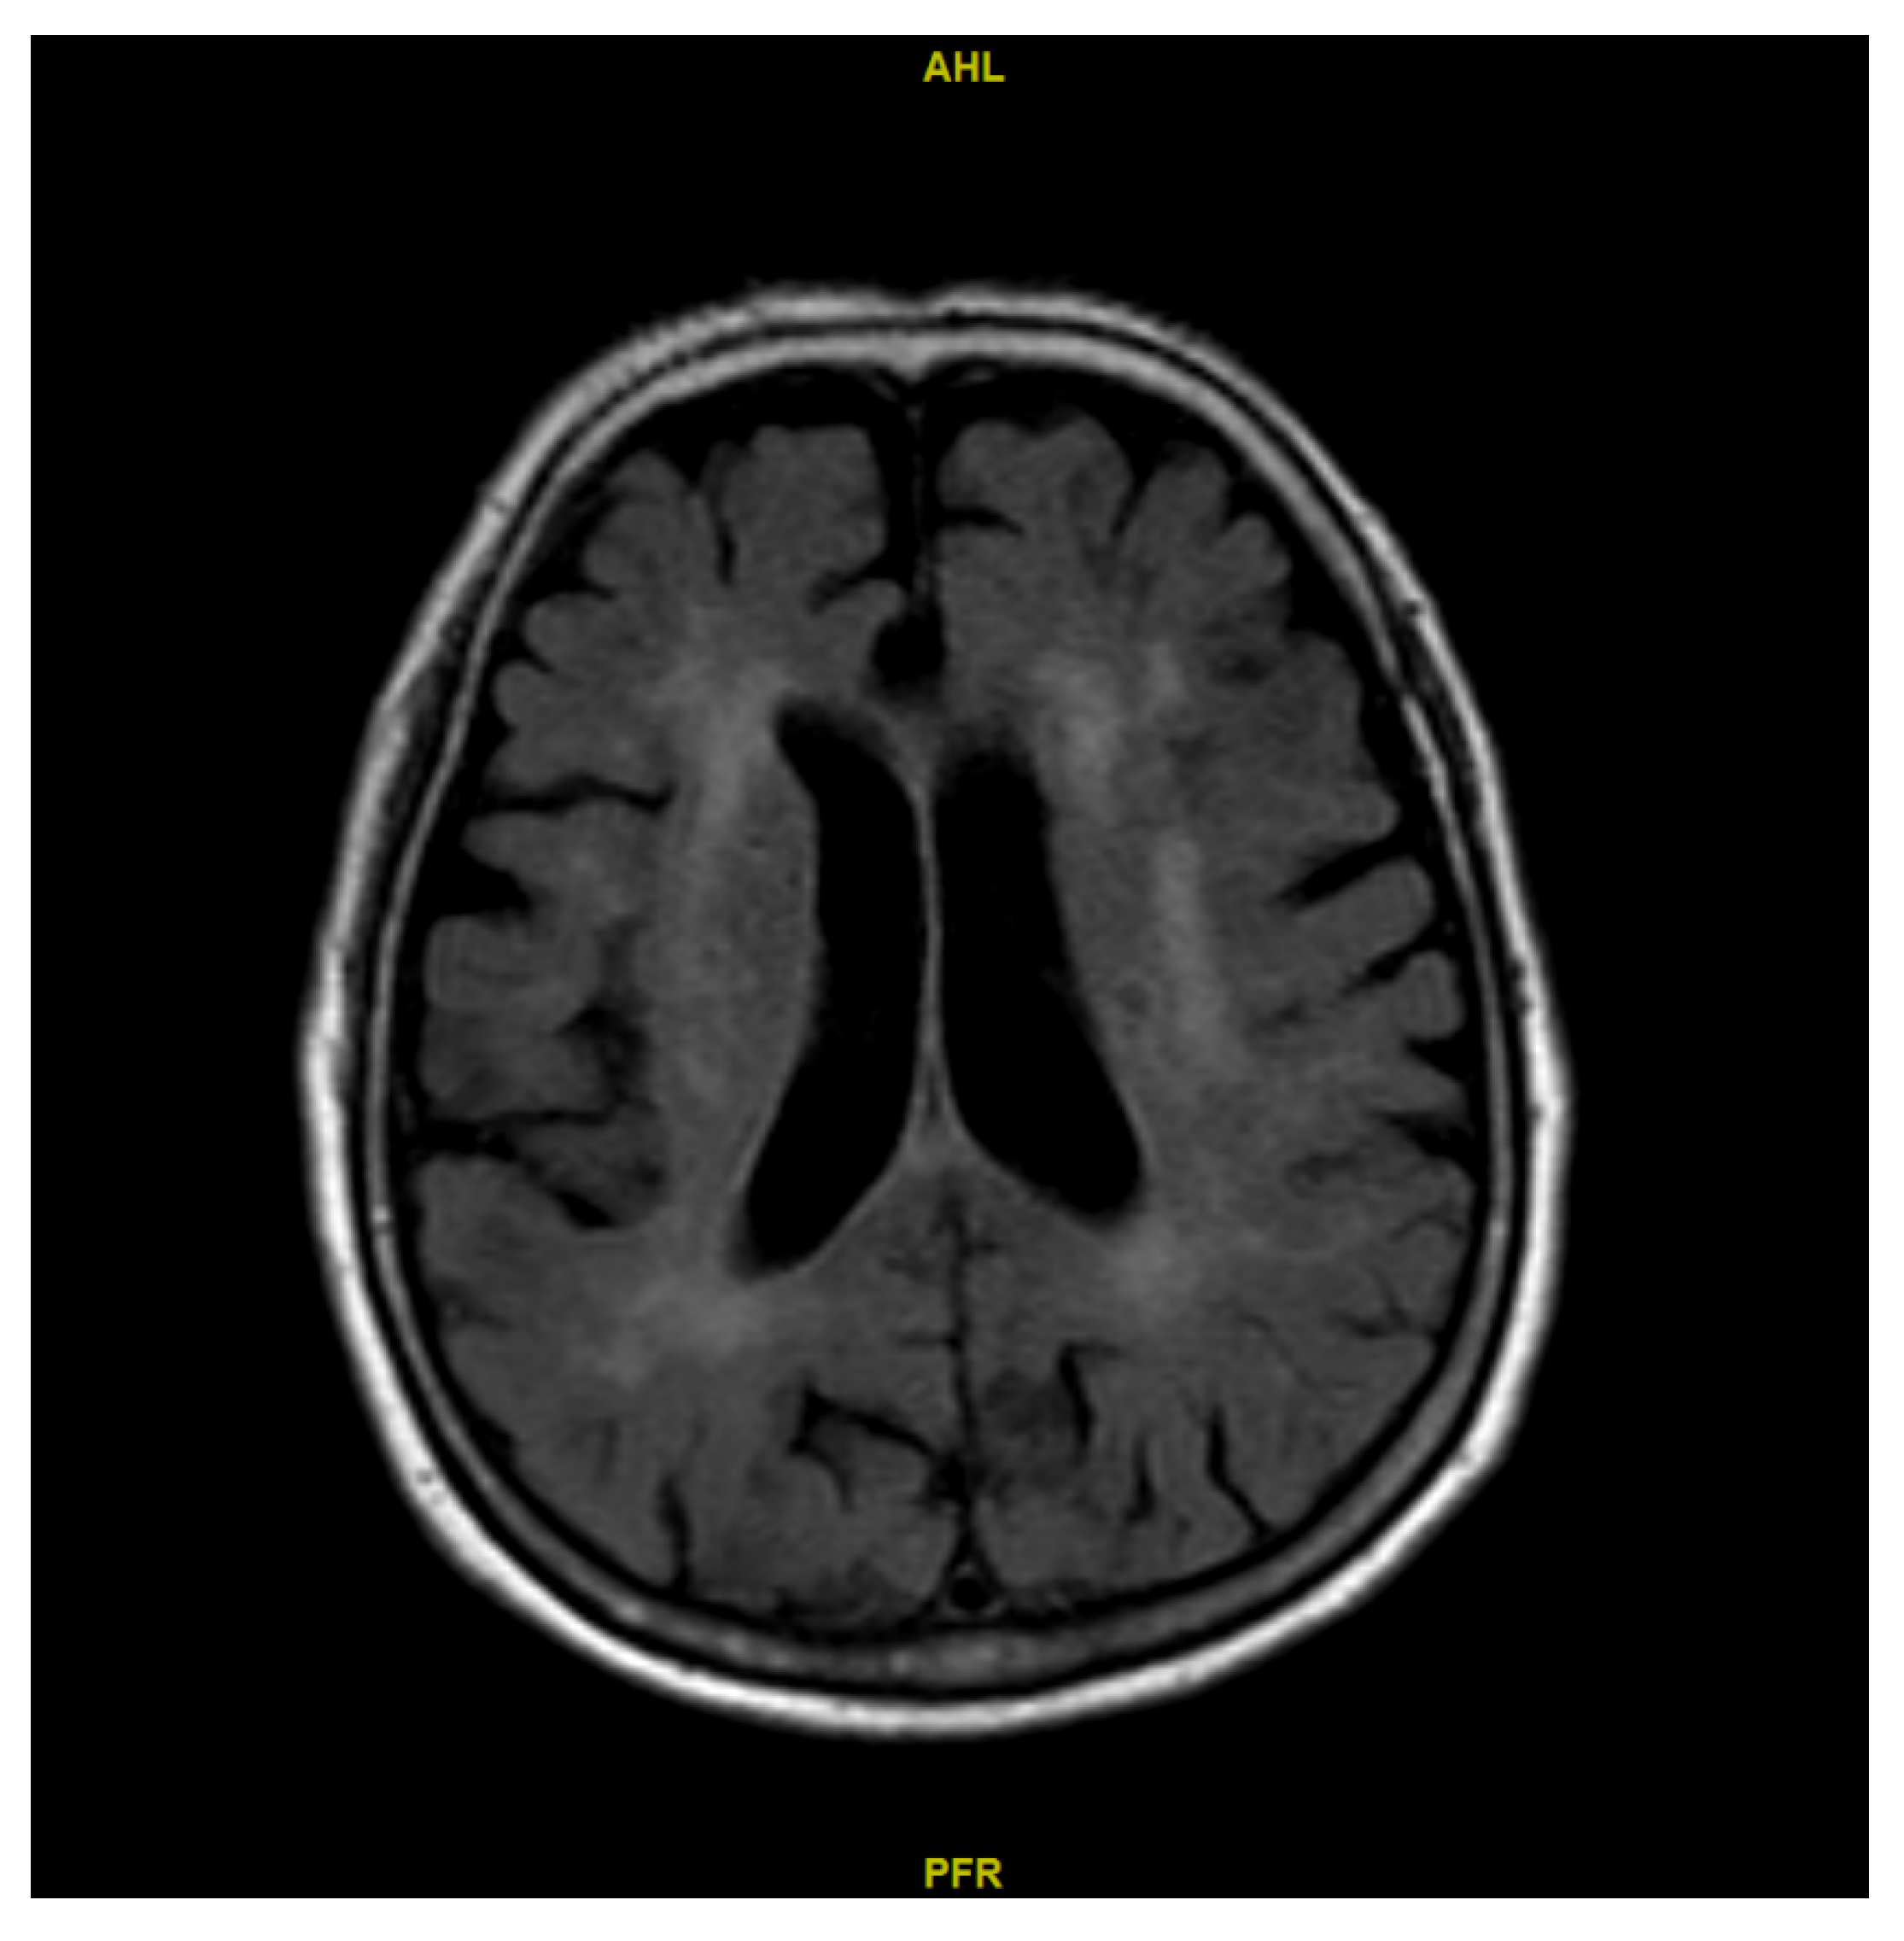

2.2. Determination of the Lateral Ventricle Volume of Both Sides

3.2. Comparison Between CBF on the Side of the LLV and the Side of the SLV Across the ROIs

3.3. Relative CBF Between the LLV and SLV Sides Across the ROIs in Patients with and Without Unilateral Stenosis